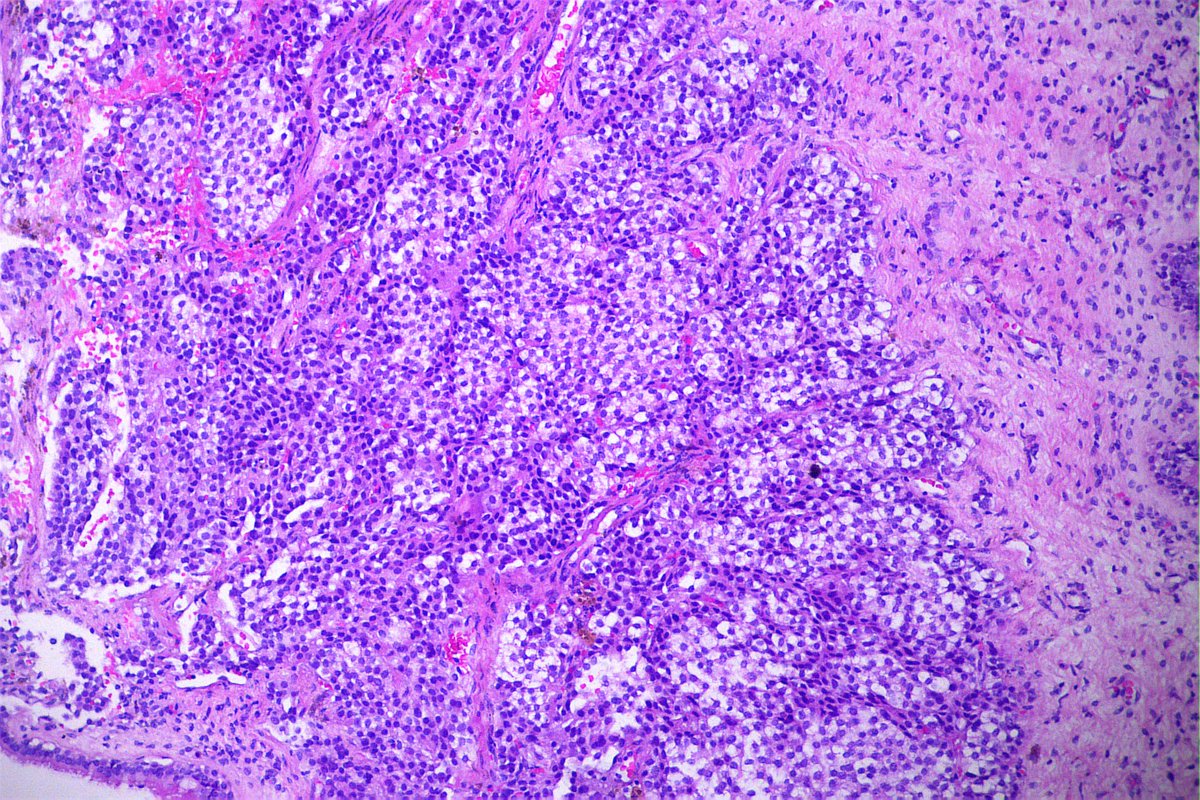

@GeronimoJrLapac

Ger么nimo Jr.

2 months

F, 47yo. The clinical information is: subepithelial lesion in the ileocecal valve. #gipath